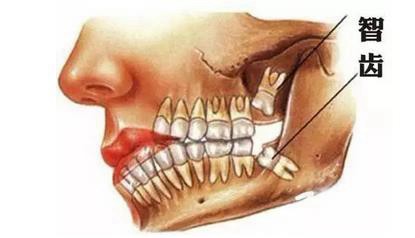

1、最不能理解的问题:智齿不疼,为什么要拔啊?

这恐怕是大家最不能理解的问题了吧,牙医也不是建议大家拔除所有智齿。只有下面情况,牙医才不建议拔除:智齿萌出完全,具有咬合功能,或者十二三岁的患者因为龋齿拔除了第一、或者第二磨牙的患者,智齿建议保留。

对于智齿已经出现过问题,或者将来可能出现问题的阻生智齿,牙医一般建议拔除。个人的解释是:阻生智齿是一颗颗肯定要爆炸的炸弹,只是牙医还不能预测什么时候会爆炸。对于牙医建议拔除的智齿,多多少少会存在一些问题,有的可能会出现智齿冠周炎、有的是会出现咬合创伤、有的会出现食物嵌塞、有的会导致邻牙出现龋齿,甚至是牙髓炎。所以对于可能要出现问题的阻生智齿,牙医建议预防性的拔除。